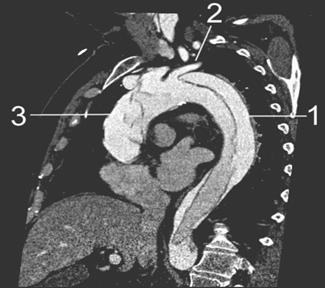

Tomografía computarizada (TC) del tórax

♦ Permite clasificar en grados:

– Tipo I: desgarro de la íntima

– Tipo II: hematoma intramural

– Tipo III: pseudoaneurisma

– Tipo IV: ruptura (Hematoma periaórtico, ruptura libre)

Figura 31. La radiografía de tórax (A) muestra un mediastino ensanchado después de una lesión contusa en el tórax (flechas). Figura 32. El aortograma en proyección anteroposterior (B) muestra un desgarro circunferencial del istmo (flecha). Se observa un pequeño pseudoaneurisma en el sitio de inserción del ligamento arterioso (punta de flecha).